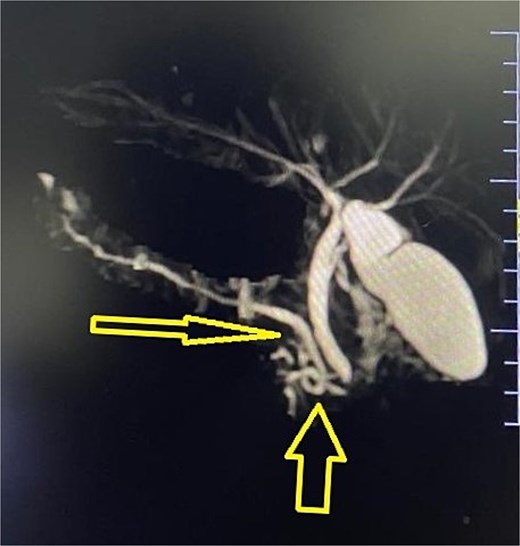

Imaging from an ultrasound indicated the main pancreatic duct was dilated to 4 mm, and a computed tomography (CT) scan confirmed dilated pancreatic duct with a Modified CT Severity Index of 4 (Fig. 1). A magnetic resonance cholangiopancreatography (MRCP) revealed a Type 3B biliary duct variation and ansa pancreatica, a looping duct connecting the main and accessory ducts draining via the minor papilla (Fig. 2).

This led to the diagnosis of acute-on-chronic pancreatitis, secondary to ansa pancreatica. The patient, initially managed conservatively, underwent Frey’s procedure through a right subcostal incision with left extension. Frey’s procedure was performed along with ductal drainage and pancreatic head decompression, as the looping duct in the pancreatic head precluded adequate treatment via endoscopic retrograde cholangiopancreatography (ERCP) or pancreatic duct papillectomy. This approach was also necessitated by the unavailability of a pediatric expert pediatric gastrosurgeon at our center. The patient was managed with fluids, analgesics, and antibiotics post-surgery, and drain removal was also done on day 5 after ensuring no pancreatic leakage. Patient remained pain-free, with normalized amylase, lipase levels, and weight gain was noted on subsequent follow-ups.